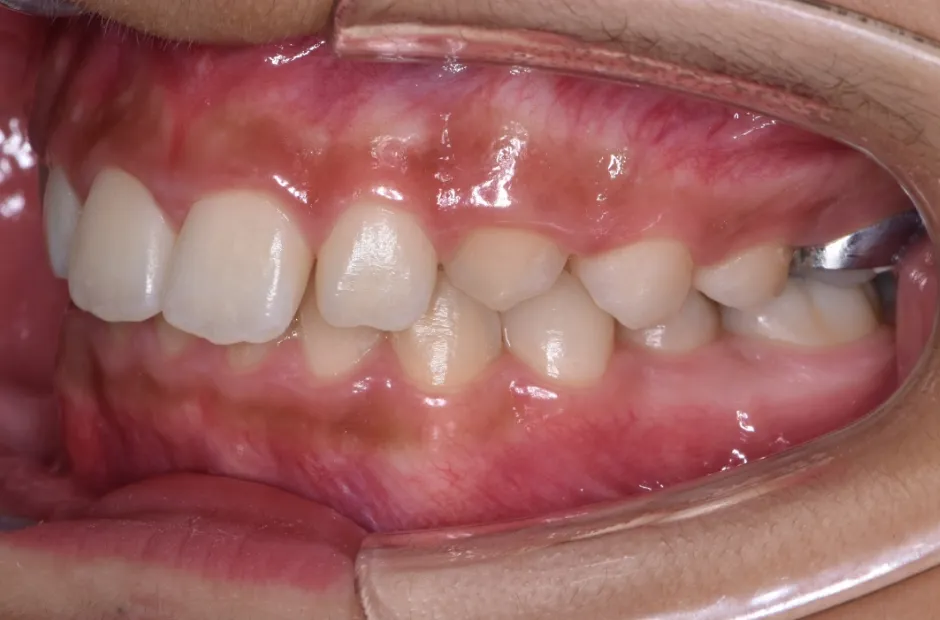

前歯部反対咬合

| 診断名・主訴 | 前歯部反対咬合 |

|---|---|

| 年齢・性別 | 14歳・男性 |

| 治療期間・回数 | 1年2か月 |

| 治療に用いた主な装置 | ブラケット矯正 |

| 抜歯部位 | なし |

| 治療費 | 60万円(税抜) |

| リスク・副作用 | 装置による違和感・疼痛・歯肉退縮・歯根吸収・虫歯のリスクなど |

治療前

治療後